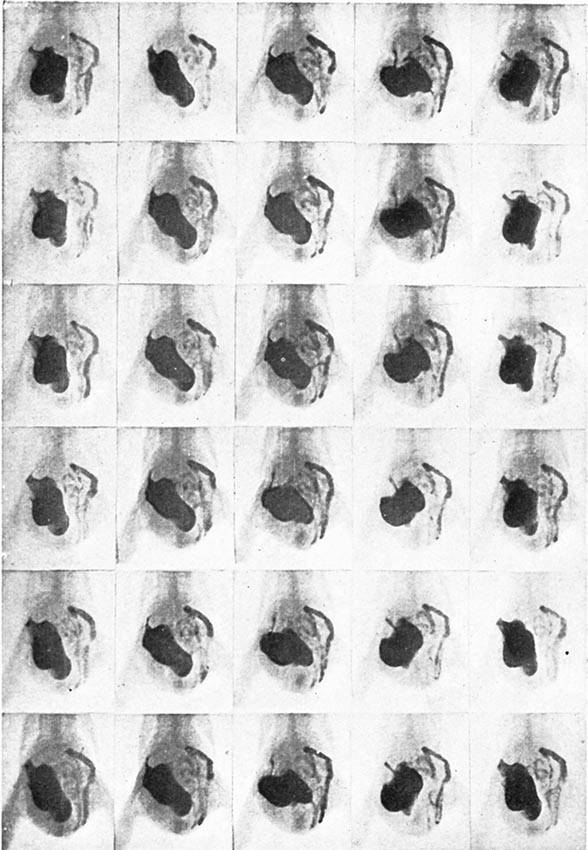

| Continuous Cinematography—Palpitations of a Rabbit's Heart | 142 |

| A wonderful X-ray Film made by M. J. Carvallo | 148 |

| Moving X-ray Pictures of the Digestion of a Fowl | 149 |